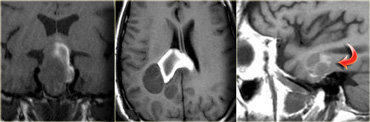

Sella/suprasellar

On the left is a list of common sellar and suprasellar tumors.

In this region it is important to keep the possibility of an aneurysm in the differential diagnosis.

On the left are images of a mass in the suprasellar cistern.

On the NECT we can see that it contains calcium.

On the T1WI there is a hyperintense area that shows no enhancement (i.e. cystic).

There are other components that show enhancement.

The tumor is complicated by a hydrocephalus.

These findings are very specific for a craniopharyngeoma.

On the left NECT and enhanced CT-images of a 33-year-old female with severe headache (worse in the a.m.), reduction in visual acuity and visual fields and papilledema.

Continue with the MR images.

Notice the normal inferiorly displaced pituitary gland.

This means it is not a macroadenoma.

The diagnosis is again a craniopharyngioma.

The differential diagnosis would include an astrocytoma and a meningioma.